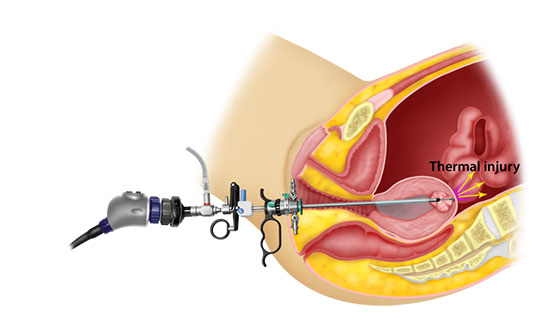

Gynaec Endoscopy

Laparoscopy

Hysteroscopy